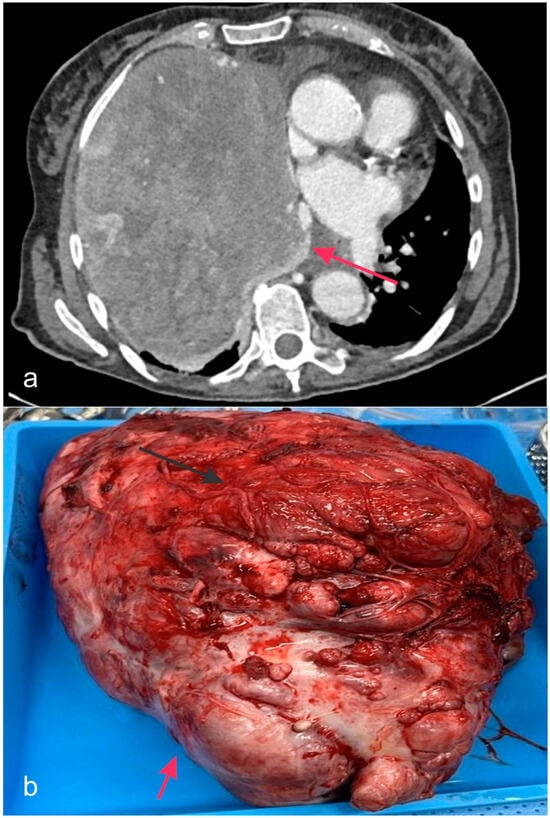

- Hill, D.A.; Ivanovich, J.; Priest, J.R.; Gurnett, C.A.; Dehner, L.P.; Desruisseau, D.; Jarzembowski, J.A.; Wikenheiser-Brokamp, K.A.; Suarez, B.K.; Whelan, A.J.; et al. DICER1 mutations in familial pleuropulmonary blastoma. Science 2009, 325, 965. [Google Scholar] [CrossRef]

- Seki, M.; Yoshida, K.; Shiraishi, Y.; Shimamura, T.; Sato, Y.; Nishimura, R.; Okuno, Y.; Chiba, K.; Tanaka, H.; Kato, K.; et al. Biallelic DICER1 mutations in sporadic pleuropulmonary blastoma. Cancer Res. 2014, 74, 2742–2749. [Google Scholar] [CrossRef] [PubMed]

- Fernández-Martínez, L.; Villegas, J.A.; Santamaría, Í.; Pitiot, A.S.; Alvarado, M.G.; Fernández, S.; Torres, H.; Paredes, Á.; Blay, P.; Balbín, M. Identification of somatic and germ-line DICER1 mutations in pleuropulmonary blastoma, cystic nephroma and rhabdomyosarcoma tumors within a DICER1 syndrome pedigree. BMC Cancer 2017, 17, 146. [Google Scholar] [CrossRef] [PubMed]

- Brenneman, M.; Field, A.; Yang, J.; Williams, G.; Doros, L.; Rossi, C.; Schultz, K.A.; Rosenberg, A.; Ivanovich, J.; Turner, J.; et al. Temporal order of RNase IIIb and loss-of-function mutations during development determines phenotype in pleuropulmonary blastoma/DICER1 syndrome: A unique variant of the two-hit tumor suppression model. F1000Research 2015, 4, 214. [Google Scholar] [CrossRef] [PubMed]